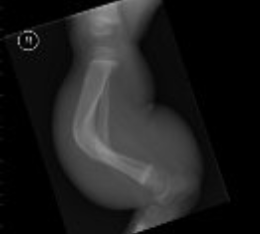

The presence of limb deformities in children can be due to many causes such as:

- Post-traumatic, after a fracture.

- Congenital, which are present from the time of birth.

- In relation to a metabolic syndrome.

- Idiopathic, where the pathological causes are unknown.

- Neuromuscular diseases.